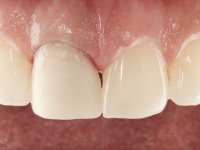

The patient came to the consultation because she did not like the “dark line next to the gums” that she had on her upper right central incisor.

Female patient, 33 years old, non-smoker. Tooth 11 with endodontic treatment rehabilitated with a crown. This crown shows an infiltrated cervical interface. The smile line was high, this area being very visible. The patient had a thick gingival phenotype and good oral hygiene.

The patient was asked to remove the infiltrated crown and make a new crown with a ceramic-coated Zr infrastructure. As aesthetically, the crown was very well achieved, the patient and her dentist showed doubts about the need or not to intervene immediately. After clarifying my position on the infiltrated interfaces, we decided to jointly intervene. In these situations, the sooner you intervene the better